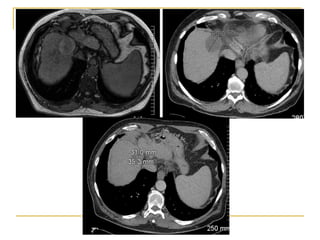

80 patients with HCC 3- 8cm (mFUP 32m)

CP A and B

< UNOS T4

23 with recurrent disease

Lesion size

52 - 3-5 cm

28 - 5-8 cm

Results

Complete ablation – 87.5%

94% cw 75% depending on size

22% local recurrence

15% vs 41% depending on size

Location near bile duct

54% distant recurrence

More frequent in recurrent HCC

Complications – 7.5% without mortality

1 tract seeding

Liu 2012 Clin Radiol 2012: 68;21

Role for microwave in larger lesions

Survival 1 2 3 5 years 81% 68% 56% 34%